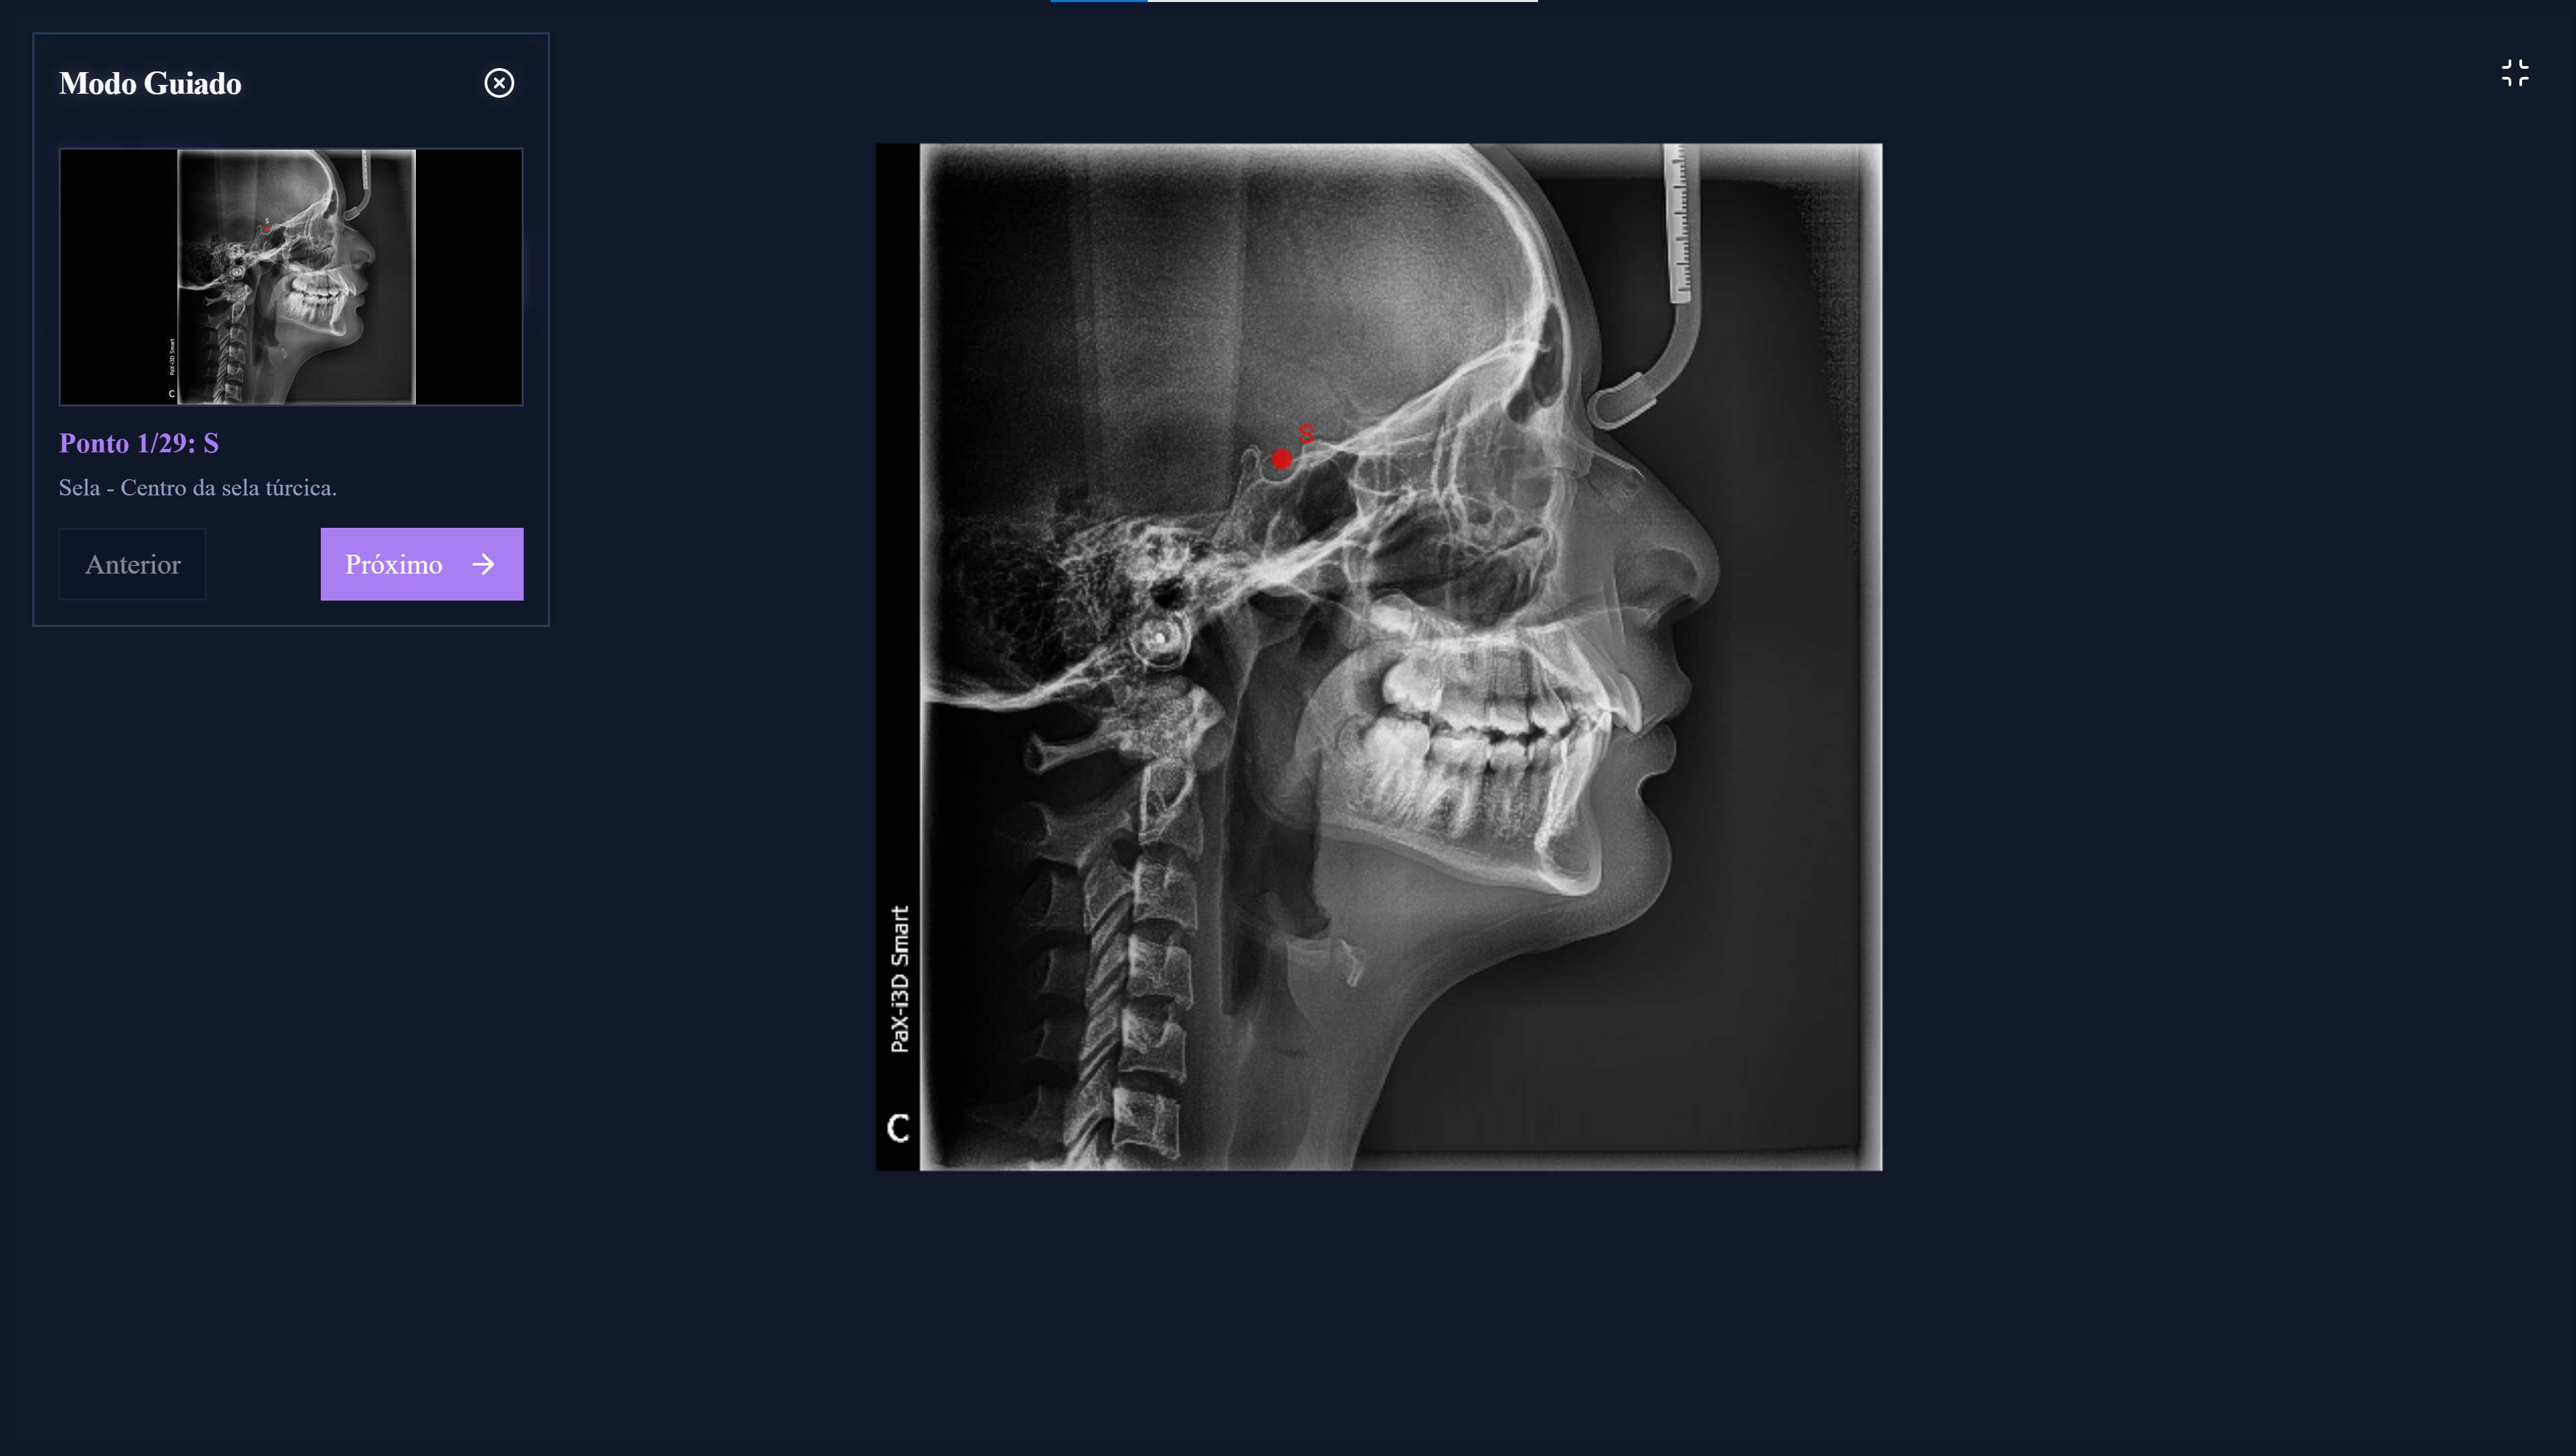

Análise Cefalométrica Manual

Realize traçados cefalométricos, calibre medidas com base em réguas e gere laudos automáticos para as principais análises (Steiner, McNamara, USP/UNICAMP, etc.).